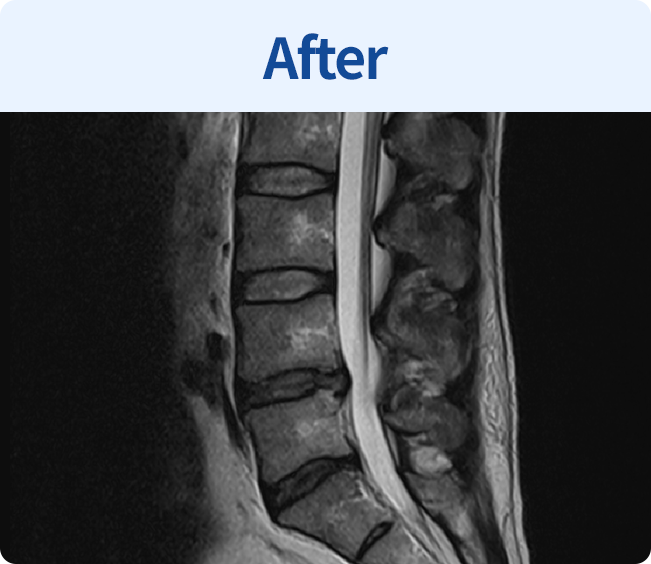

척추유합술

미세현미경을 통해 손상된 뼈와 인대조직을 제거하고 디스크의 역할을 해줄 인조 케이지를 삽입해

불안정한 척추체를 나사못으로 고정하는 수술 (척추 전방 골유합술, 척추 후방골유합술)